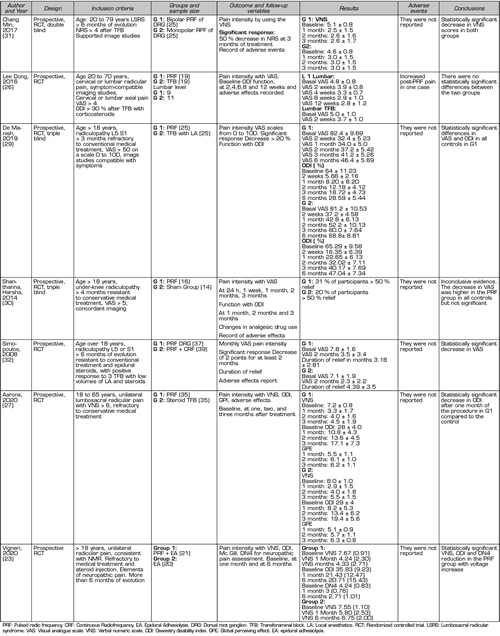

In the present literature search, eight prospective randomized studies (23,26-32) and nine quasi-experimental studies (33-41), of before-and-after type, were found evaluating the efficacy of PRF of the DRG. It should be noted that, in the former, there is high clinical heterogeneity in relation to the control group used as a comparator, and to other interventions used before and after the evaluated procedure (e.g., steroids or local epidural anesthetics) (Table I). This heterogenicity makes difficult to interpret results and prevents the proper conduct of a meta-analysis (3). Table II shows the parameters used in the application of pulsed radiofrequency in the eight randomized prospective studies.

Table I. Randomized controlled studies to measure efficacy and safety profile of PRF of the DRG

Lee et al. (2016) compared the effects of PRF of the DRG with those of transforaminal steroid injection in 20 patients with lumbosacral radicular pain divided into 2 groups of 9 and 11 patients, respectively (26). They use the Visual Analogue Scale (VAS) and the Oswestry Disability Index (ODI) as evaluators of results over a three-month period, finding an improvement in these scales when compared with baseline measurements, but without finding statistically significant differences between the procedures evaluated (26).

Arons et al. (2020) also use transforaminal steroid injection as a control group to assess the analgesic effect in PRF of DRG in patients with unilateral lumbosacral radicular pain (27). The authors conducted a randomized, double-blind, controlled study in 70 patients divided into two groups of 35, using the PRF of the DRG for 180 seconds in the study group. The studied variables were the global perceiving effect (GPE), The Verbal Numeric Scale (VNS) and the ODI, evaluated at 30, 60, and 180 days. The procedures were repeated at 30 days in those patients in whom the improvement was below 50 % in relation to baseline values. The authors found a larger decrease in disability in the group treated with PRF of the DRG after 30 days compared with the steroid injection group. Whereas, at 180 days, the percentage of patients with pain improvement was slightly higher in this group than in patients treated with PRF (67 % versus 60 %). No complications were reported in this study (27).

Koh et al. (2015) studied the effects of adding PRF of DGR to transforaminal epidural steroid injection in 62 patients with lumbosacral radicular pain refractory to non-interventional treatments in two study groups of 31 patients each (27). In both groups, the injection of 20 mg of triamcinolone was conducted after 3 cycles of 120 seconds of PRF or a simulation of it (sham group). Although the authors found improvement in all the parameters evaluated (VNS, GPE, ODI) when comparing the results obtained after treatment with baseline measurements, they found no statistically significant differences when comparing both groups during the 3-month control period. However, if the baseline results obtained with VNS were adjusted to zero, the decrease obtained at 3 months was higher in the group where the PRF of the DRG was performed (p = 0.038) (28).

De et al. (2019) conducted a randomized prospective triple-blind study, using transforaminal injection of 1 ml of bupivacaine 0.5 % as an active control group and PRF of DRG in three cycles for 180 seconds as a study group (29). Fifty patients with lumbosacral radicular pain refractory to conservative treatment (pharmacological, physical therapy), with a positive response prior to a selective prognostic block, were equally distributed in the two established groups. The VAS and ODI were used as outcome assessment parameters at two weeks of the procedure and at 1, 2, 3 and 6 months. One hundred percent of patients in the PRF group had a decrease of more than or equal to 2 points in VAS and a significant decrease in the ODI at all evaluation intervals. In the control group, 80 % of patients showed a decrease at 3 months and only 28 % at 6 months. The authors concluded that the 180-second application of PRF in the DRG results in a mid-term improvement of pain intensity and functional status of patients with lumbosacral radicular pain, when the previous performance of a selective prognostic block with local anesthetics is positive, discarding non-responsive patients (29).

Shanthanna et al. (2014) conducted a double-blind prospective study, using as a control group a simulation of the procedure or sham group, in which radiofrequency cannulas were placed in the neuroforamina, even with sensory and motor stimulation, but without finally performing the PRF, constituting a true placebo group (30). In the study group, a cycle of PRF was performed for 120 seconds, using 0.5 cm active tip needles. The authors found a decrease in VAS at all evaluation intervals (1 day, 1, 2, and 3 months) but did not reach statistical significance between groups. In this study, the number of patients was low, 16 in the PRF group and 15 in the control group, which required 15 months to obtain recruitment. Due to the small difference in the percentage of patients experiencing a 50 % or larger decrease in VAS between the groups, the authors decided to discontinue the study because of the excessive time required to complete recruitment, according to their judgment. In this study, no previous selection was performed based on the response to selective blocks with local anesthetics (30).

Vigneri (2020) randomized two groups of patients: PRF of the DRG was performed in 21 patients for 240 seconds and increased the voltage between 65 and 80 and then hyaluronidase, local anesthetics,

and betamethasone were administered while the control group received only adhesiolysis and PRF was simulated (23). The group in which the PRF was performed showed a significant decrease in the Visual Numerical Scale at 1 month and 6 months after treatment. Although the increase in voltage could have a positive impact on the final analgesic result, further studies are needed with more patients and with a design that

allows the performance of the increase in voltage to be assessed as the only variable (23).

Finally, there are studies comparing different radiofrequency modalities applied on the DRG. Simonopulus et al. (2008) conducted a prospective randomized study in 76 patients with chronic lumbosacral radicular pain refractory to conventional treatment, clustering them into two groups: One group treated with PRF of the DRG only, and the other group treated with the same procedure followed by continuous RF (32). The authors found no statistically significant differences in the decrease in VAS scores between the groups two months after the procedures were performed. Interestingly, they found no neurological complications in the group in which continuous RF was used (32).

Chang et al. (2017) conducted a prospective randomized study to compare the PRF modality of unipolar (single-cannula) versus bipolar DRG, by placing two RF cannulas near the DRG (31). The recruited patients had lumbosacral radicular pain refractory to transforaminal steroid injection. The authors found a decrease in pain intensity measured by VNS at one, two and three months of the procedures, with a larger decrease in pain in the group treated with bipolar modality (p = 0.037). A production of higher intensity and denser electric fields in this group is suggested as an explanation for the larger analgesic effect (31).